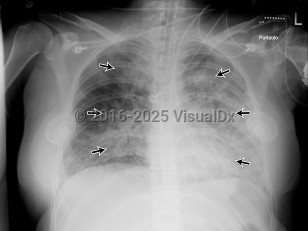

Anasarca, 50-59 year old Female

Pericardial effusionPericardial effusion